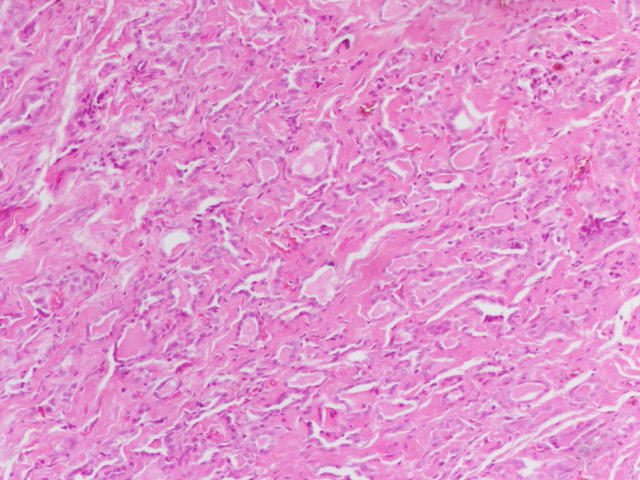

Multiple aldosterone producing nodules are associated with an increased risk of biochemical recurrence in the contralateral adrenal (top row). This specimen also contained an unrelated ganglioneuroma (bottom row) with typical macroscopic/microscopic features. #endopath #GUpath